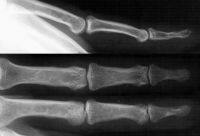

| Xrays of a painful glomus

tumor of many years duration, showing a local impression extending

through the dorsal and palmar cortices of the distal phalanx. |